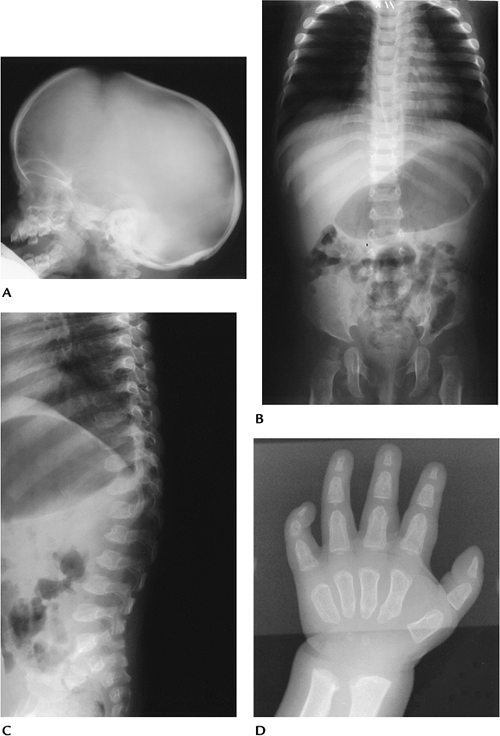

FIGURE 15-28 Hurler Syndrome (MPS-IH). (A) Lateral radiograph of the skull shows a large “J”-shaped sella and underdeveloped mastoids. Sinuses are hypoplastic. (B) AP radiograph of the spine and pelvis demonstrates expanded anterior ribs, hypoplastic ilia, and coxa valga. (C) Lateral radiograph of the spine shows hypoplastic vertebrae at the thoracolumbar junction with anterior beaking. (D) Hand radiograph demonstrates thick short metacarpals and phalanges with pointing of the proximal metacarpals.